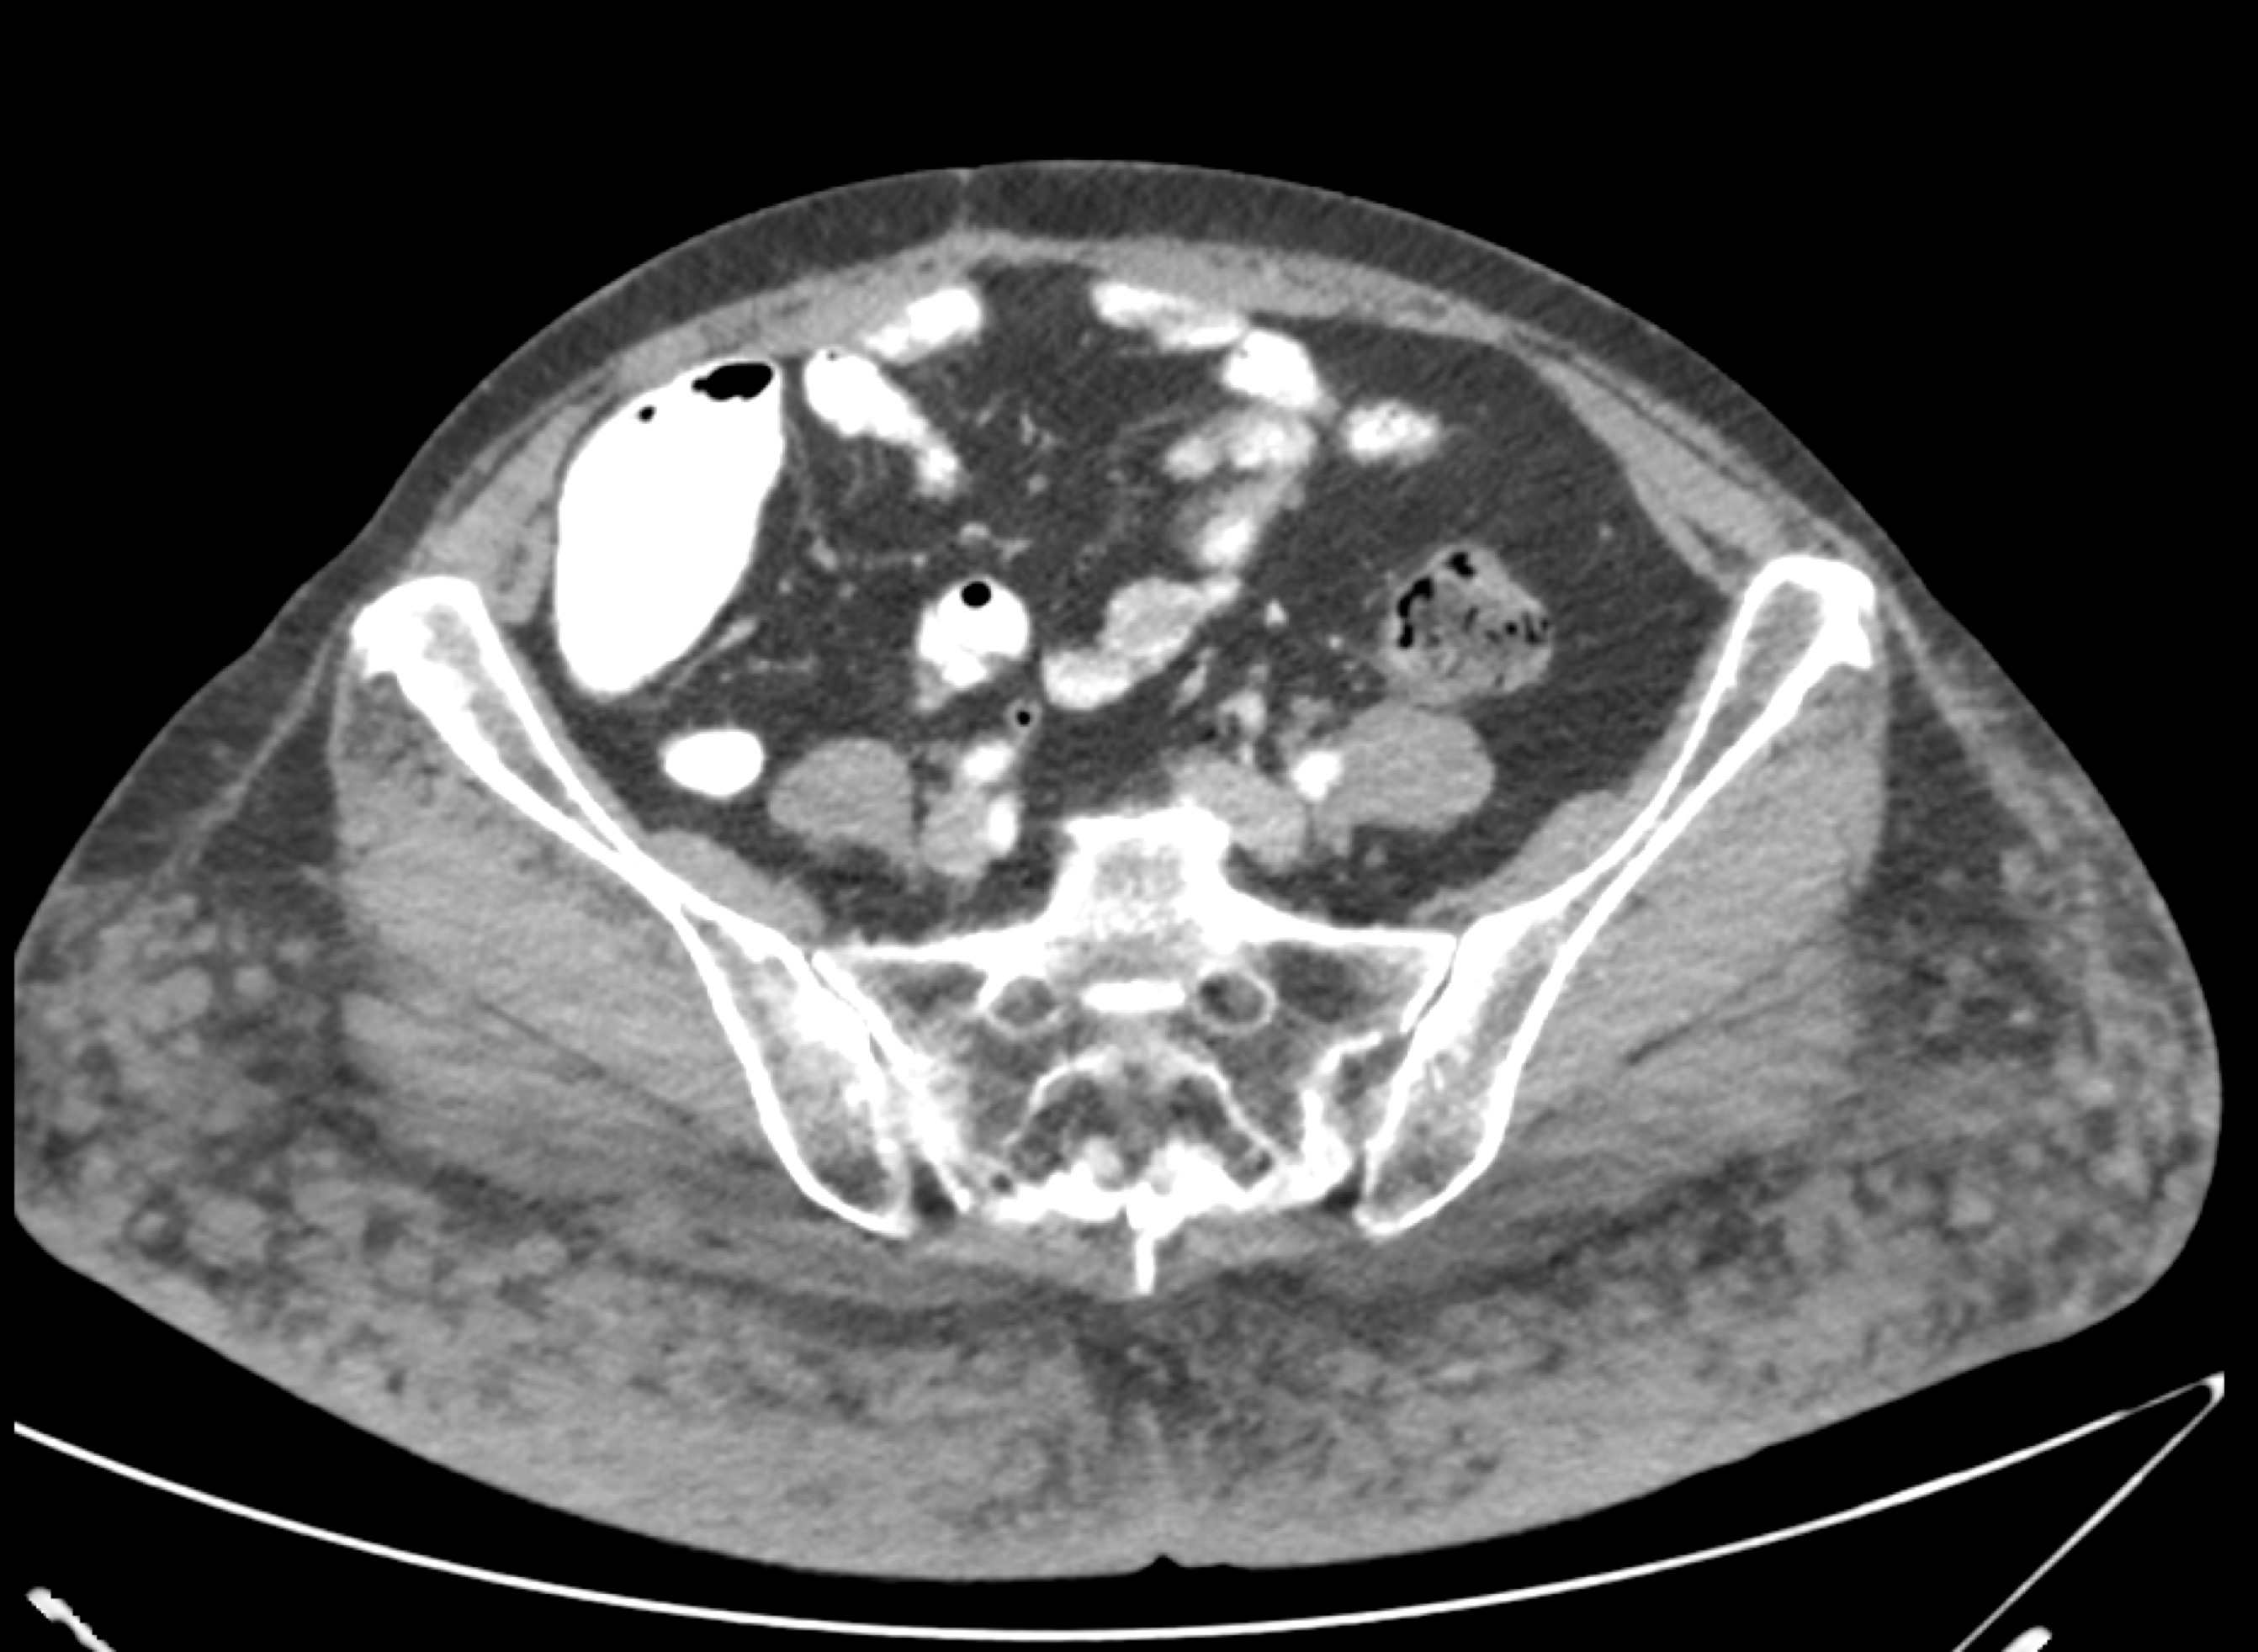

4) In this patient with sickle cell disease the most likely diagnosis is?

lymphoma

renal cell carcinoma

renal abscess

MEST tumor